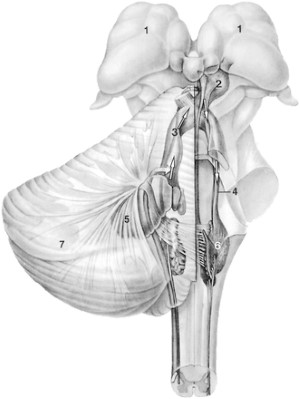

Thoái hoá phì đại nhân trám (hypertrophic olivary degeneration, HOD) được xem là sự thoái hóa xuyên khớp thần kinh (transsynapse) xảy ra sau tổn thương ở tam giác Guillain và Molaret (Hình 8), như là chảy máu trần cầu não (tegmentum pontis) hoặc chảy máu nhân răng. Thoái hoá phì đại nhân trám được thấy ở phía cùng bên với chảy máu trần cầu não và ở bên đối diện với chảy máu nhân răng. Các vùng cường độ tín hiệu cao trên ảnh T2-W xuất hiện sau cơn đột quỵ 3 tuần, và tồn tại dài đến 8 năm sau. Phì đại của các nhân trám dưới nhìn thấy 5-15 tháng sau cơn đột quỵ. Các bất thường nhân trám hai bên có thể thấy khi chảy máu trần cầu não liên quan đến cuống tiểu não trên (Hình 9). Các thay đổi bệnh lý chính của HOD bao gồm thoái hóa hốc của các neuron to lên, phì đại các tế bào hình sao, và tăng sinh tế bào thần kinh đệm (gliosis). Các vùng cường độ tín hiệu cao ở các nhân trám dưới là do thành phần nước tăng lên và tăng sinh các tế bào thần kinh đệm [17].

Hình 8. Hình minh hoạ tam giác Guillain và Molaret. ION = Inferior olivary nucleus (nhân trám dưới). Red nucleus = nhân đỏ. Dentate nucleus = nhân răng. (AJNR 2000 21: 1073-1077 )

Ghi chú thêm về phì đại thoái hoá nhân trám

Sơ đồ của đường đi của nhân trám-dải nhân răng, hay tam giác Guillain và Mollaret. Các mũi tên chỉ đường đi của tam giác này, khi có tổn thương cắt đứt mối liên hệ này sẽ gây thoái hoá phì đại nhân trám. 1, Đồi thị; 2, Nhân đỏ; 3, cuống tiểu não trên; 4, Dải trung tâm trần cầu não (central tegmental tract); 5, Nhân răng; 6, Nhân trám; 7, tiểu não (December 1999 Radiology, 213, 814-817)

Mối liên hệ cụ thể giữa tổn thương nguyên phát (chủ nếu là nhồi máu, xuất huyết, hoặc thoái hoá) và sự tiến triển thoái hoá nhân trám theo một trong ba dạng mô tả dưới đây và dễ hiểu hơn nhờ sơ đồ minh hoạ trên. Khi tổn thương nguyên phát khu trú ở dải trung tâm trần cầu não thì phì đại nhân trám cùng bên (Hình 10), bởi vì chỉ có các sợi cùng bên bị tác động. Khi tổn thương nguyên phát ở nhân răng hoặc ở cuống tiểu não trên thì thoái hoá nhân trám đối bên. Khi tổn thương liên quan đến cả hai dải trung tâm trần cầu não và cuống tiểu não trên thì thoái hoá nhân trám cả hai bên.